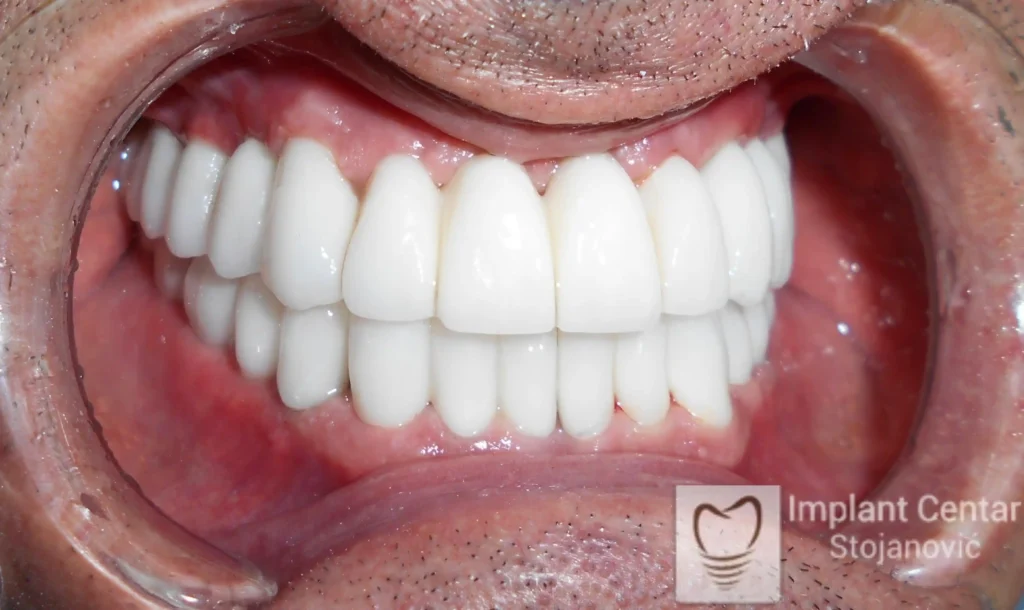

Pacijent sa rascepom usne, nepca i alveolarnog grebena uspešno je rehabilitovan fiksnim protetskim radom na implantatima. Pre dolaska u našu ordinaciju, pacijent je u gornjoj vilici nosio totalnu protezu preko preostalih zuba, dok je u donjoj vilici bio zbrinut parcijalnom mobilnom protezom. Tokom višegodišnje potrage za adekvatnim rešenjem, pacijent nije uspeo da pronađe zadovoljavajuću terapijsku opciju ni u zemlji ni u inostranstvu.

Nakon detaljnog kliničkog pregleda i analize radioloških snimaka, izrađen je sveobuhvatan plan terapije sa ciljem uklanjanja mobilnih proteza i postizanja maksimalne funkcionalne i estetske rehabilitacije. Zbog loše biološke vrednosti preostalih zuba, doneta je odluka o njihovom vađenju i ugradnji dentalnih implantata.

Poseban terapijski izazov predstavljalo je premošćavanje defekta nastalog usled rascepa, kao i ograničena količina raspoložive kosti u gornjoj vilici. Primenom većeg broja implantata i odgovarajućih procedura nadoknade kosti, postignuta je stabilna osnova za fiksni protetski rad.

Tokom perioda oseointegracije, pacijent je bio zbrinut fiksnim privremenim krunicama, čime je već pet dana nakon intervencije obezbeđena potpuna funkcionalna i estetska rehabilitacija. Nakon završetka perioda integracije implantata, izrađeni su definitivni cirkonijum-keramički mostovi na implantatima.

Pacijent je izuzetno zadovoljan postignutim rezultatom, navodeći da po prvi put jasno oseća svoje nepce tokom žvakanja, kao i da se smeje sa punim samopouzdanjem.